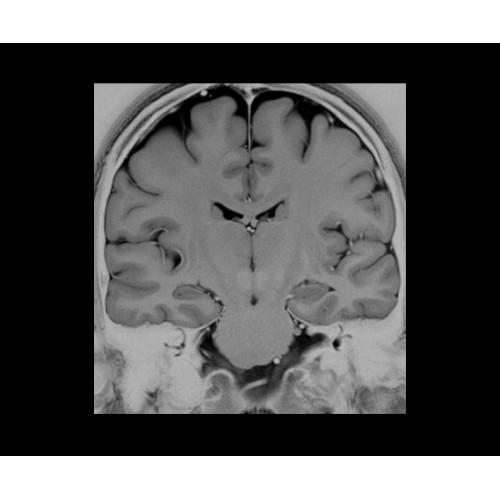

SIGNA PET/MR 3.0T — это гибридная система, в которой совмещаются две принципиально разные технологии — магнитно-резонансную томографию (МРТ) и позитронно-эмиссионную томографию (ПЭТ). Система отличающийся высокой чувствительностью и эффективностью и предназначена для диагностики в области онкологии, неврологии, кардио-васкулярных исследований, исследований воспалительных процессов.

Компания GE Healthcare представляет революционную, полностью интегрированную систему SIGNA PET/MR1, в которой сочетаются времяпролетная технология (TOF) и возможности напряженности магнитного поля 3.0 Тл. Мы поможем вам поднять исследования на более высокий уровень. SIGNA PET/MR позволяет достичь впечатляющей точности и скорости исследований, а благодаря новейшей технологии реконструкции Q.Clear2 качество изображений улучшается в два раза. Кроме того, в систему включен полный набор клинических приложений и гибких катушек для проведения любых видов исследования, открывая для вас возможности визуализации, о которых вы даже не догадывались.

Система SIGNA PET/MR предлагает впечатляющие клинические возможности и открывает доступ к наиболее полным пакетам программных приложений.

• Специальный пакет приложений для измерения и сравнения объемных изображений ЦНС с нормами поможет вам в диагностике нейродегенеративных заболеваний, а дополнительные инструменты визуализации — в постановке точного диагноза с помощью бета-амилоидов и радиоизотопных маркеров ФДГ.